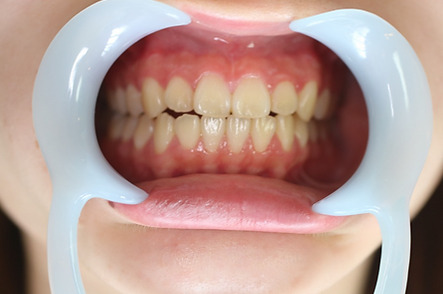

1矯正・マウスピース【治療例2】

治療前